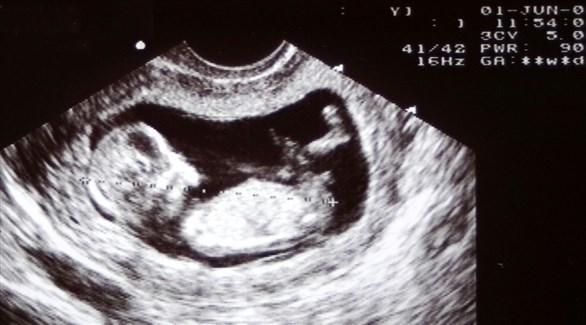

ويرجح أن تسمع الأم دقات قلب جنينها بالسونار في الأسبوع الـ 16 من الحمل، وربما تمرر الطبيبة المسبار حول بطن الأم لو استمرت حركة الجنين، لسماع دقات القلب.

وتعتبر حركة الجنين داخل الرحم من أفضل المؤشرات على أنه بخير.